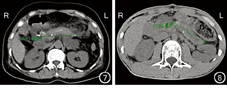

病例1和病例2均顺利完成MPP,手术时间分别为470 min和400 min;术中出血量分别为200 mL和100 mL;2例患者术中均未输血。病例1和病例2术后血糖分别为5.4~11.8 mmol/L和5.9~11.3 mmol/L。病例1术后发生腹腔感染,经抗感染治疗后好转出院;病例2术后恢复顺利,无并发症发生。病例1和病例2均无胰瘘及围术期死亡;术后住院时间分别为12 d和8 d。病例1术后胰腺标本组织病理学检查结果示胰头、胰尾浆液性囊腺瘤(图5)。病例2术后胰腺标本组织病理学检查结果示胰头、胰尾组织胰管轻度扩张伴多发结石,胰管周围慢性炎症细胞浸润(图6)。病例1和病例2例术后复查CT示保留胰腺长度分别为8.5 cm和8.3 cm(图7,图8)。病例1和病例2例均获得随访,随访时间分别为5个月和7个月。随访期间2例患者均无新发糖尿病,无需胰酶替代治疗。2例患者均于术后5个月行腹上区CT平扫及增强复查,中段胰腺血运良好,无肿瘤及结石复发征象。